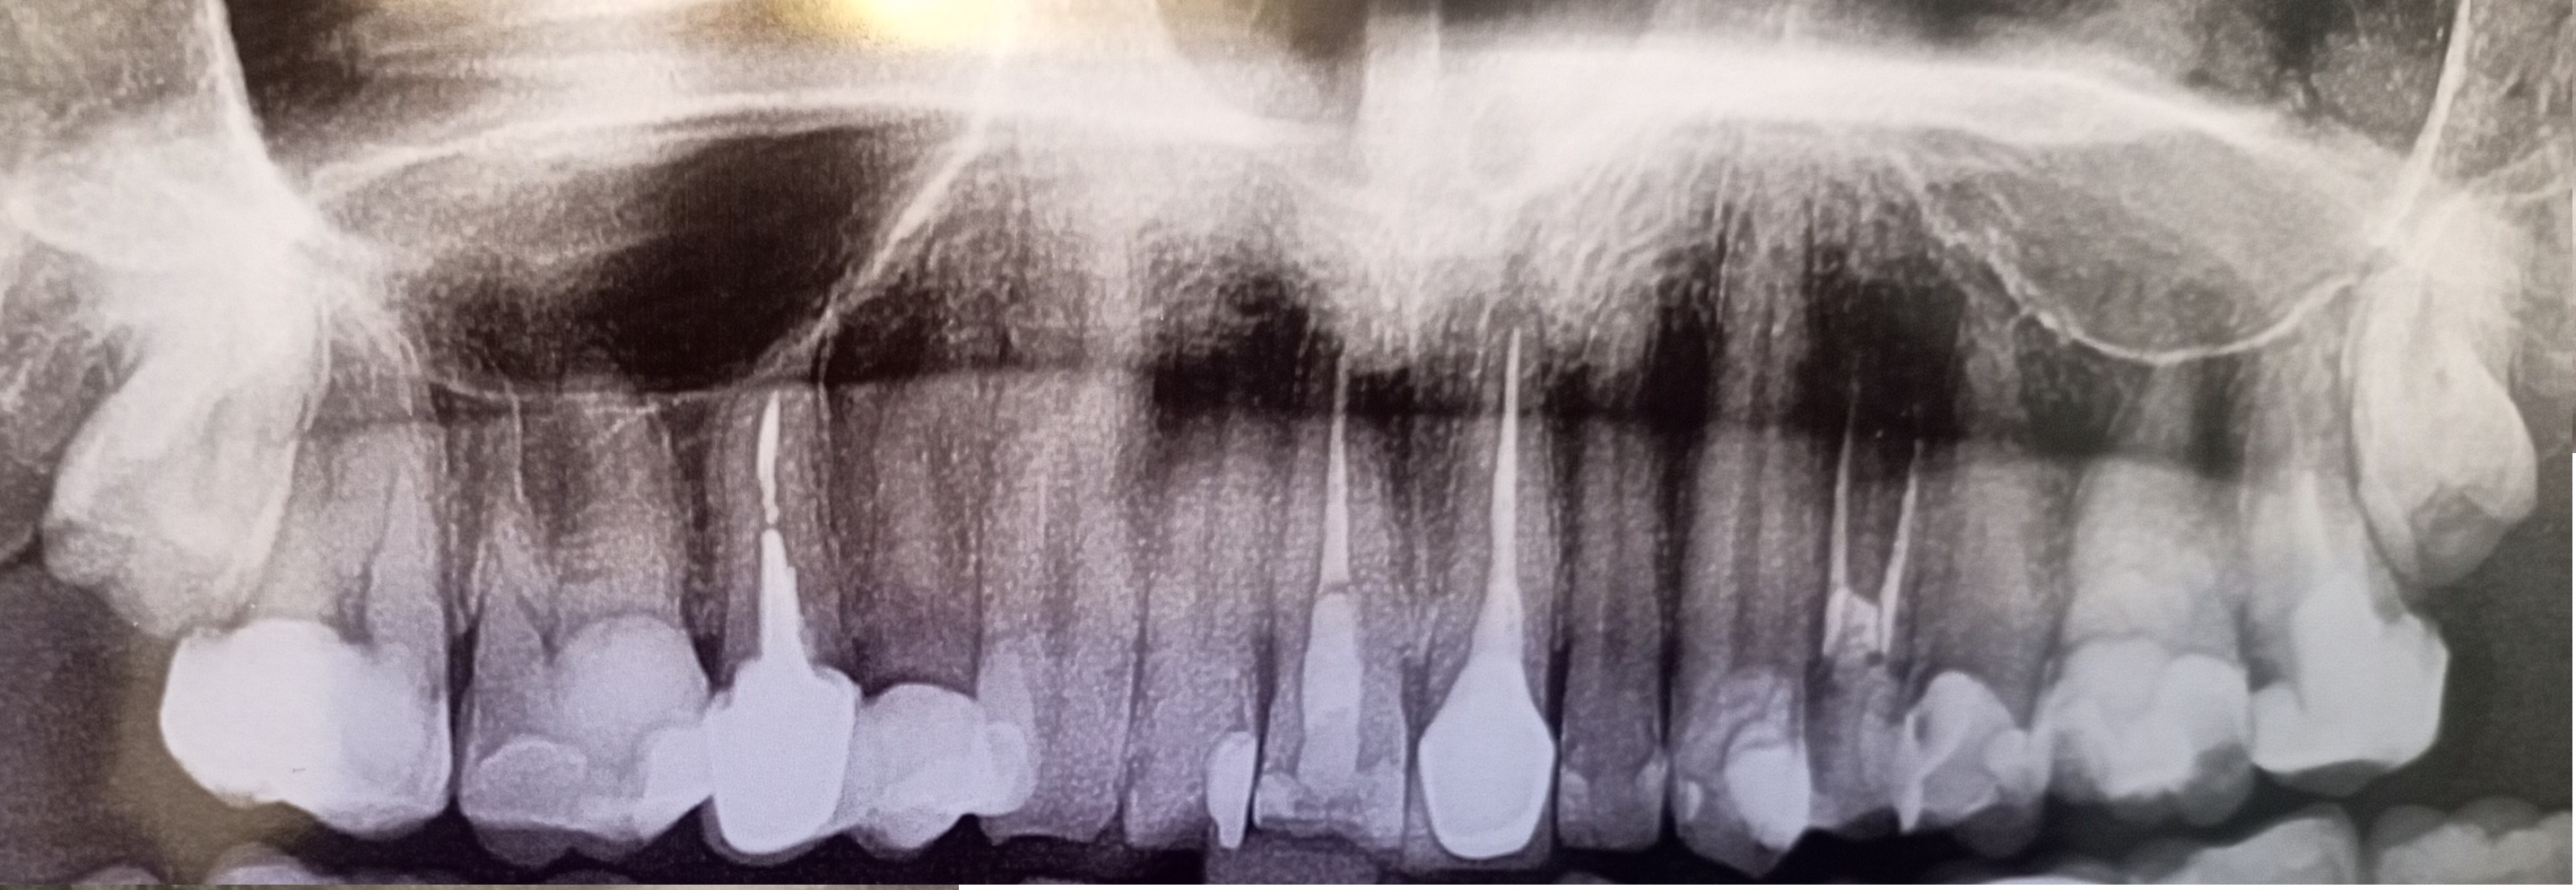

1000070960.jpg 313Кб, 1117x832

1117x832

1000070961.jpg 180Кб, 882x704

882x704

Зуб пятерка. Возможно такое вылечить, анонче? Отклолся как то, вообще не болит.